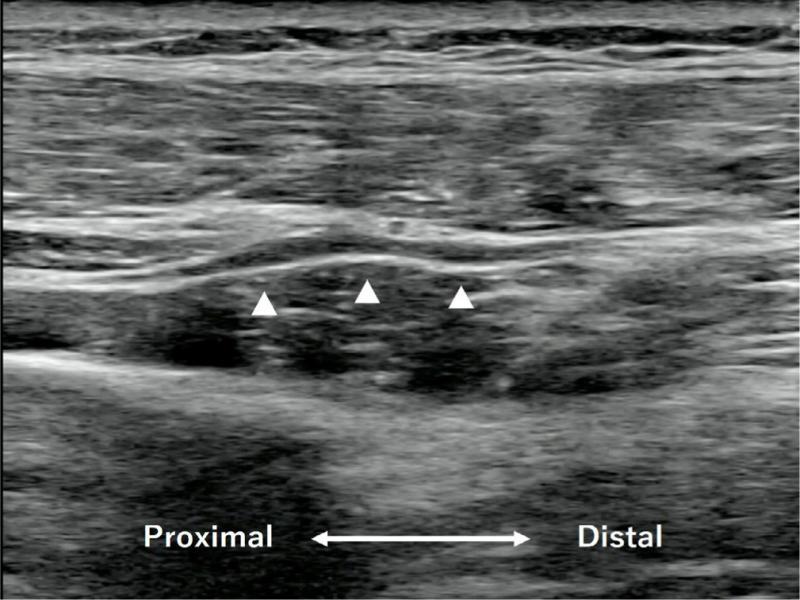

Ultrasonographic examination (Sonimage HS1, Konica Minolta, Tokyo, Japan) was performed, and multiple stenotic lesions interrupted by hyperechoic bands within the fascicles of the PIN were found 5 cm distal to the lateral epicondyle. The multiple stenotic lesions were located at the distal end of the supinator muscle, and nothing was found at the entrance point of the supinator (Fig. 2). We suspected that these lesions were hourglass-like constrictions in the PIN.

Fig. 2.

A longitudinal image of the proximal dorsal forearm. There were multiple constrictions of the PIN at the level of the distal end of the supinator muscle. The constrictions were bordered by swelling of the PIN (arrowheads)